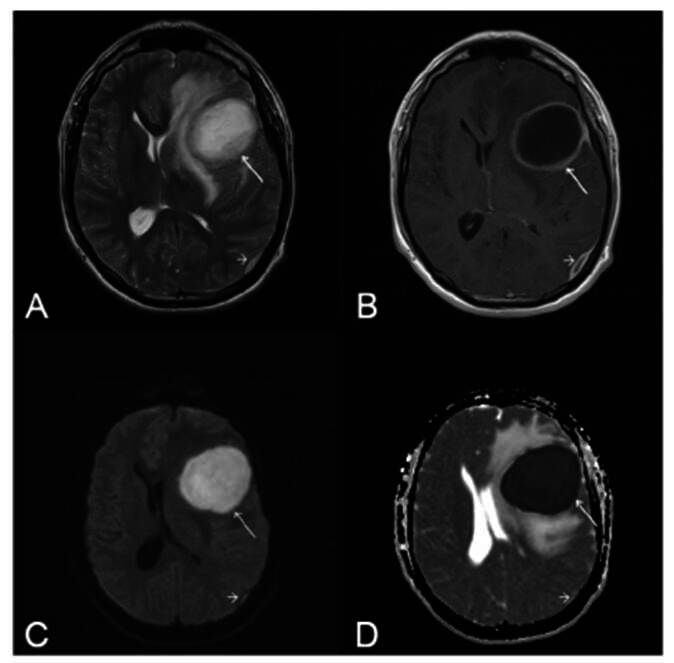

Streptococcus constellatus, a member of the Streptococcus anginosus group, is a commensal bacterium that causes pyogenic infections, particularly abscesses. This report describes the case of a 28-year-old immunocompetent man who developed a brain abscess and epidural empyema after pneumonia. MRI suggested an abscess, which was confirmed by culture, revealing S. constellatus. Treatment included abscess drainage and ceftriaxone administration, which led to a full recovery. Diagnosis is challenging because of overlapping features with other bacteria. Imaging and culturing are crucial for identification. This case highlights the importance of considering S. constellatus in central nervous system infections, even in immunocompetent individuals.